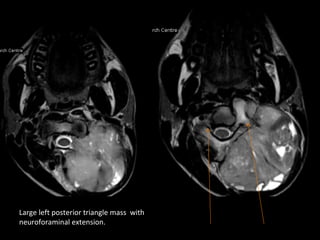

Large left posterior triangle mass with

neuroforaminal extension.

Tumor extension seen within neural foramen   Normal angio

and inside spinal canal.

Diagnosis -Neurogenic tumor

• MRI is ideal in assessing intraspinal /